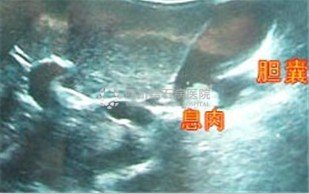

襄阳妇科病医院专家表示,人流时间又称胆囊隆起样病变或胆囊肿瘤,从胆囊肿瘤的意义上分析人流时间,又可分为真性肿瘤和假性肿瘤两种。

所谓真性肿瘤,指胆囊本身的腺体、肌 层增生引起的人流时间,这是一种胆囊的真正意义上的肿瘤。所谓假性肿瘤,是指由于肝胆清理功能失调、紊乱引起胆固醇积聚、结晶,胆囊慢性炎症引起炎性增生,胆囊、胆汁异常 改变引起的其它增生性病变。

特点二:隐蔽攻击性:强人流时间多无症状,85%以上的患者都是在例行体检中发现。在检 查上,2mm以下的息肉在CT和核磁共振中难以发现或常常漏诊。